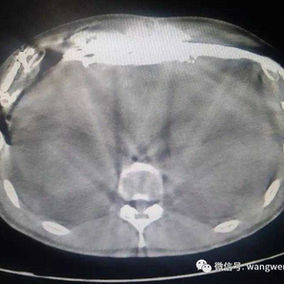

The chest wall exhibits a large area of prominent and bilaterally symmetrical protrusion, predominantly in the upper half. There are also mild depressions on both sides of the lower half of the chest wall.

First, two 3 cm incisions were made on each side of the chest wall, followed by a 2 cm incision along the old surgical scar in the middle of the chest wall. Two bars were then placed on the protruding bone structures of the chest wall to perform the Wenlin procedure. Since the anterior chest wall is a rigid whole, correcting and pressing down the protrusion in the upper chest often causes a secondary depression below it. To address this, a third bar was inserted into the chest cavity to perform the Wung procedure, thereby elevating the depressed areas. Ultimately, the patient’s chest wall deformity was corrected, and the surgery achieved a satisfactory outcome.